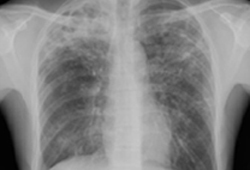

Chest x-ray

A chest x-ray should be obtained early in the evaluation of chronic cough.[38] Although it is not diagnostic of the most common causes, findings may quickly divert the evaluation to causes of greater gravity, such as structural lung diseases. These include lung cancer, pulmonary fibrosis, tuberculosis, bronchiectasis, pneumonia, aspiration, and sarcoidosis.[Figure caption and citation for the preceding image starts]: Chest x-ray showing hyperinflation in a patient with COPD. The hyperinflation is caused by the emphysema component of COPD, rather than the chronic bronchitis that underlies symptoms of coughFrom the personal collection of Dr M. A. Sharifabadand, SUNY at Stony Brook School of Medicine, Department of Pulmonary and Critical Care Medicine, Mineola, New York and Dr J. P. Parsons, The Ohio State University Medical Center, Columbus; used with permission [Citation ends].com.bmj.content.model.assessment.Caption@65a65855[Figure caption and citation for the preceding image starts]: Chest x-ray showing multiple miliary lung metastases (arrows). The primary tumour was a thyroid carcinomaE. Dick, Student BMJ. 2001;9:10-12 [Citation ends].com.bmj.content.model.assessment.Caption@25657fee[Figure caption and citation for the preceding image starts]: Chest x-ray showing left hilar carcinoma (arrow)From: E. Dick, Student BMJ. 2000;8:358-360 [Citation ends].com.bmj.content.model.assessment.Caption@567b9fef[Figure caption and citation for the preceding image starts]: Chest x-ray showing a cavitating right hilar carcinoma (arrow)E. Dick, Student BMJ. 2001;9:10-12 [Citation ends].com.bmj.content.model.assessment.Caption@3d6fa55[Figure caption and citation for the preceding image starts]: Chest x-ray in a patient with bronchogenic carcinoma showing a left-sided pleural effusionFrom: R. Thakkar, Student BMJ. 2001;9:458 [Citation ends].com.bmj.content.model.assessment.Caption@5b46acec[Figure caption and citation for the preceding image starts]: Chest x-ray showing interstitial fibrosis in a patient with amiodarone pulmonary toxicityFrom the personal collection of Dr A. Pataka and Professor P. Argyropoulou, Aristotle University, Thessaloniki, Greece; used with permission [Citation ends].com.bmj.content.model.assessment.Caption@2c3c94b0[Figure caption and citation for the preceding image starts]: Chest x-ray showing pulmonary tuberculosis with cavitationFrom the personal collection of Dr M. Narita, Department of Pulmonary and Critical Care Medicine, University of Washington [Citation ends].com.bmj.content.model.assessment.Caption@3dd7f84b[Figure caption and citation for the preceding image starts]: Chest x-ray showing multiple discrete nodules throughout both lungs (one of which is circled) in a patient with miliary tuberculosisE. Dick, Student BMJ. 2001;9:10-12 [Citation ends].com.bmj.content.model.assessment.Caption@23fa6365[Figure caption and citation for the preceding image starts]: Chest x-ray with lack of normal tapering producing a tram line in a patient with bronchiectasisFrom the personal collection of Dr S.M. Bhorade, University of Chicago Medical Center; used with permission [Citation ends].com.bmj.content.model.assessment.Caption@36b415f2[Figure caption and citation for the preceding image starts]: Chest x-ray with dilated and thickened airways in a patient with bronchiectasisFrom the personal collection of Dr S.M. Bhorade, University of Chicago Medical Center; used with permission [Citation ends].com.bmj.content.model.assessment.Caption@78e208fa[Figure caption and citation for the preceding image starts]: Chest x-ray showing increased opacification of the right perihilar region and superior segment of the right lower and upper lobes consistent with worsening aspiration pneumoniaFrom the personal collection of Dr R. Kanner, University of Utah School of Medicine [Citation ends].com.bmj.content.model.assessment.Caption@71be2c1f[Figure caption and citation for the preceding image starts]: Portable chest x-ray with bibasilar opacities, worse on the right than the left, in a patient with hospital-acquired pneumoniaFrom the personal collection of Dr F. W. Arnold, Division of Infectious Diseases, Department of Medicine, University of Louisville School of Medicine [Citation ends].com.bmj.content.model.assessment.Caption@2c704497[Figure caption and citation for the preceding image starts]: Chest x-ray showing early ill-defined opacities of the right upper lobe above the minor fissure consistent with early changes of aspiration pneumoniaFrom the personal collection of Dr R. Kanner, University of Utah School of Medicine [Citation ends].com.bmj.content.model.assessment.Caption@23fa54d0[Figure caption and citation for the preceding image starts]: A. Portable upright chest x-ray before aspiration; B. Chest x-ray 1 hour after aspiration, showing bilateral diffuse alveolar infiltrates, worse at the bases on the right sideFrom the personal collection of Dr S. Murgu and Dr H. Colt, University of California at Irvine Medical Center [Citation ends].com.bmj.content.model.assessment.Caption@7860be3a[Figure caption and citation for the preceding image starts]: Chest x-ray showing bilateral hilar adenopathy in a patient with sarcoidosisFrom the personal collection of Dr M.P. Muthiah, Division of Pulmonary and Critical Care and Sleep Medicine, University of Tennessee [Citation ends].com.bmj.content.model.assessment.Caption@31e94b4e